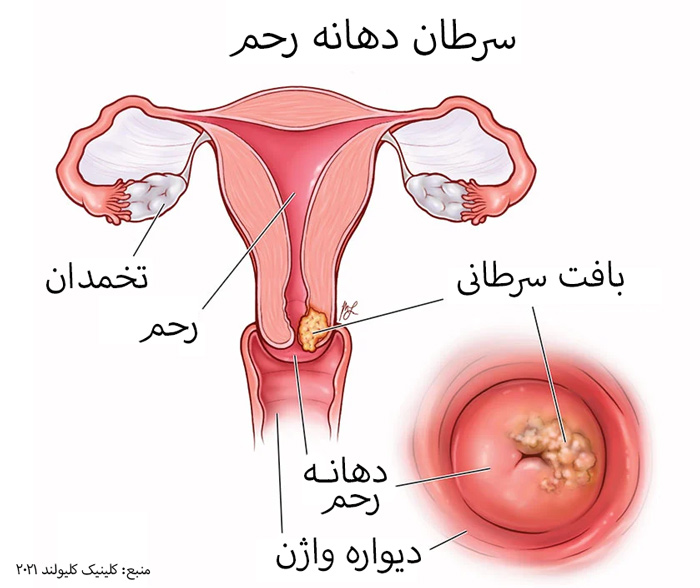

قیمت: 32٬000 تومان - دسته بندی فایل: علوم پزشکیپاورپوینت سرطان دهانه ی رحم

فروش ویژه پاور پوینت حرفه ای سرطان دهانه ی رحم با تخفیف استثنایی فقط 63 هزار تومان تعداد اسلاید: 22 اسلاید